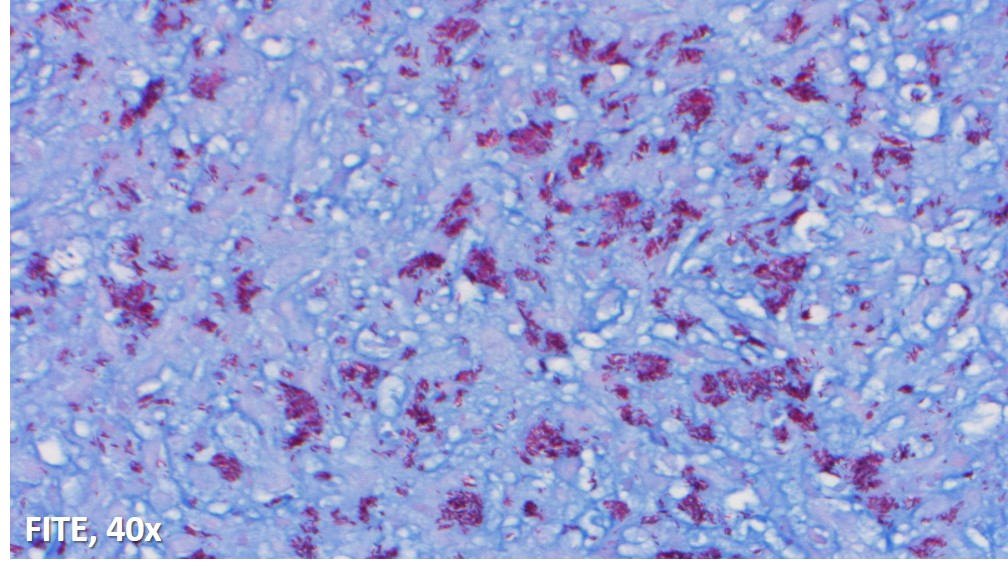

Immunoperoxidase and special stains were performed on this case. The cells were diffusely positive for CD45 and CD163, and negative for keratin cocktain, S100, CD1a and CD30. AFB and Fite were positive for acid fast bacilli, and highlighted abundant organisms. The findings were consistent with an infectious lymphadenitis, and most suggestive of a nontuberculous mycobacterial infection.